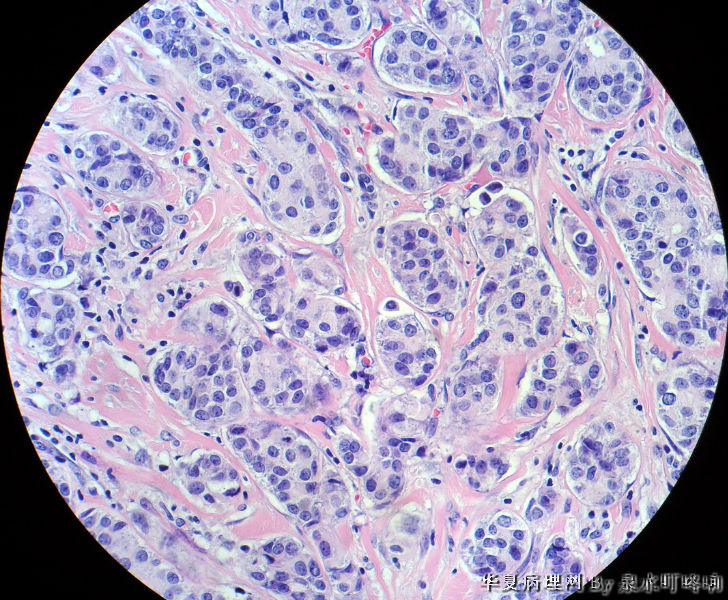

• 右腋下包块图1

图1

女,60岁,右腋下肿物两年余。

大体:灰白带皮组织一块,大小约3.8×2.2×1.4厘米,皮肤呈橘皮样改变,切面灰白,质韧。

乳腺浸润型导管癌(副乳起源?还是原发灶在乳腺,腋下为癌结节?)

最后诊断:浸润性导管癌(分化较低),考虑来自乳腺尾叶或副乳恶变。